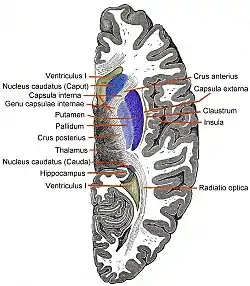

Coronal section of brain through intermediate mass of third ventricle. (Putamen labeled at top.) | |

The putamen is a structure in the forebrain. Along with the caudate nucleus it forms the dorsal striatum. The caudate and putamen contain the same types of neurons and circuits – many neuroanatomists consider the dorsal striatum to be a single structure, divided into two parts by a large fiber tract, the internal capsule, passing through the middle. The putamen, together with the globus pallidus, makes up the lentiform nucleus. The putamen is the outermost portion of the basal ganglia. These are a group of nuclei in the brain that are interconnected with the cerebral cortex, thalamus, and brainstem. Basal ganglia include the dorsal striatum, substantia nigra, nucleus accumbens, and the subthalamic nucleus.

Caudate nucleus

Globus pallidus